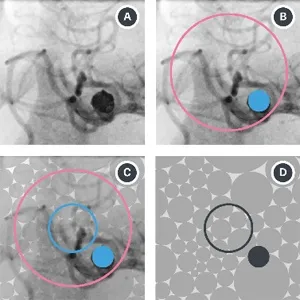

Foot Interaction Concepts to Support Radiological Interventions Journal Article

In: i-com, vol. 17, no. 1, pp. 3–13, 2018, ISSN: 2196-6826, (Publisher: Oldenbourg Wissenschaftsverlag).

abstract = {During neuroradiological interventions, physicians need to interact with medical image data, which cannot be done while the hands are occupied. We propose foot input concepts with one degree of freedom, which matches a common interaction task in the operating room. We conducted a study to compare our concepts in regards to task completion time, subjective workload and user experience. Relative input performed significantly better than absolute or rate-based input. Our findings may enable more effective computer interactions in the operating room and similar domains where the hands are not available.},